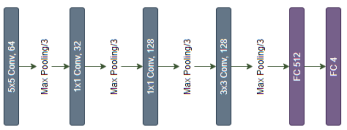

This model consisting of only 6-layer model contains 423,460 parameters for training. Four consecutive convolutional layers following two fully connected layers with ReLU activation function are embraced in this model. Filter size is used sequentially 64-32-128-128 for convolution layers possessing strides 2-1-1-1 on each dimension. Output is filtered by connected layers activated with sigmoid function. Each 3x3 max-pooling layer bundled with a convolution layer helps significantly reducing the function. The model network is shown in Fig 3 and the model configuration in Table IV.

Trained model is then used for prediction and LIME is introduced as the explain-er for this model. 100 samples are used with 5 top-levels to explain the model as there is

| Conv5D-64 | 224x224x3 | 110x110x64 | 4864 |

| Max Pooling | 110x110x64 | 54x54x64 | 0 |

| Conv1D-32 | 54x54x64 | 54x54x32 | 2080 |

| Max Pooling | 54x54x32 | 26x26x32 | 0 |

| Conv1D-128 | 26x26x32 | 26x26x128 | 4224 |

| Max Pooling | 26x26x128 | 12x12x128 | 0 |

| Conv3D-128 | 12x12x128 | 12x12x128 | 147584 |

| Max Pooling | 12x12x128 | 5x5x128 | 0 |

| Dropout | 5x5x128 | 5x5x128 | 0 |

| Max Pooling | 5x5x128 | 2x2x128 | 0 |

| Flatten | 2x2x128 | 512 | 0 |

| Dense 1 | 512 | 512 | 262656 |

| Dropout | 512 | 512 | 0 |

| Dense 2 | 512 | 4 | 2052 |

| Total Param | 423460 | ||

| Total Trainable Param | 423460 |